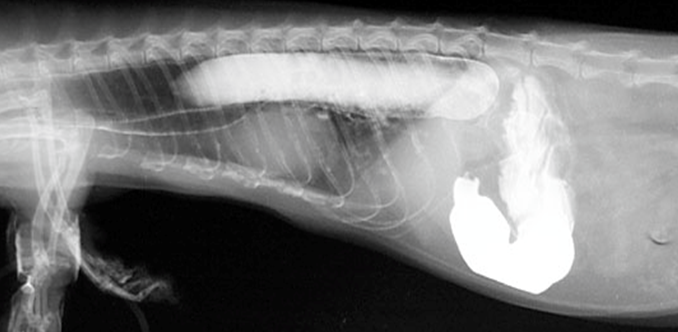

鑑別診断には食道または胃腸の異物、胃炎、および呼吸器疾患が含まれます。X線検査では食道が拡張あるいはガスが貯留しており、確定診断のために硫酸バリウムまたはイオヘキソール(経口投与 [PO] で 8~10 mL/kg)を投与します。フェレットは注射器で強制的にバリウムを摂取しますが、食道破裂の可能性がある場合には、バリウムの代わりにイオヘキソールを使用します。造影剤が食道の輪郭を描出し、巨大化していることで診断されます。

造影剤が食道全体に浸潤しているような像が得られると食道炎を併発している可能性が高いです。